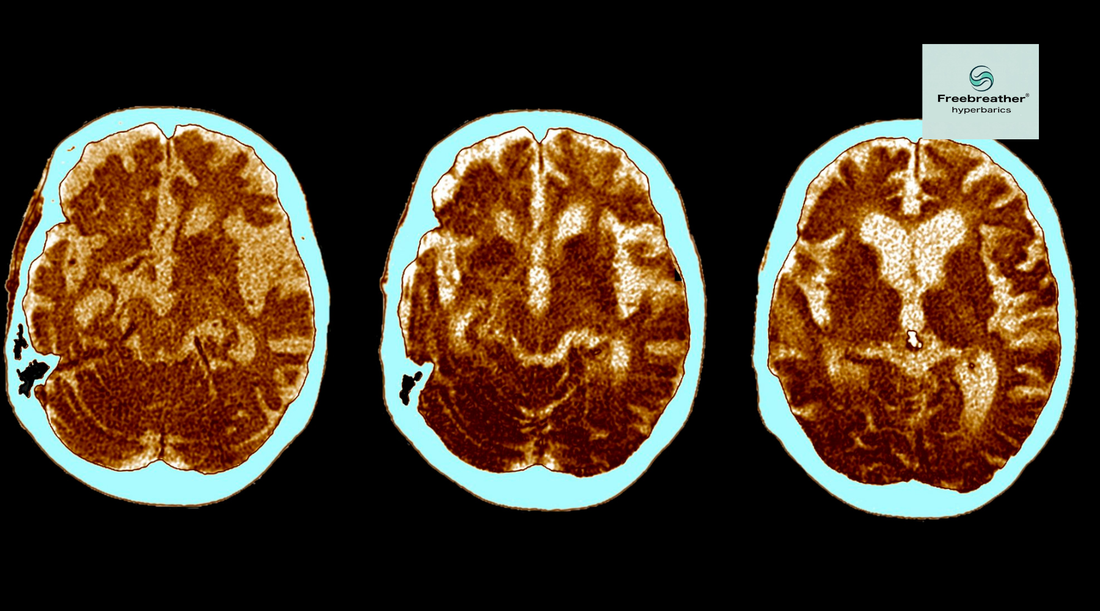

Neurodegenerative diseases — including Alzheimer’s disease, Parkinson’s disease, multiple sclerosis (MS), and amyotrophic lateral sclerosis (ALS) — are among the most challenging medical conditions. They involve the progressive loss of neurons, leading to memory decline, movement disorders, or loss of function. While there is no cure for these conditions, research suggests that hyperbaric oxygen therapy (HBOT) can play a complementary role in improving brain oxygenation, reducing inflammation, and supporting neuronal survival.

The brain is highly dependent on oxygen. Even slight reductions in oxygen availability can accelerate neuronal damage. In many neurodegenerative diseases, reduced blood flow and chronic inflammation worsen the brain’s ability to heal and regenerate. HBOT, by delivering pure oxygen at higher-than-normal pressures, increases oxygen dissolved in plasma and cerebrospinal fluid. This makes oxygen more available to damaged or hypoxic (low oxygen) brain regions.

3. Neuroplasticity and Repair: Studies show HBOT can stimulate  Neurogenesis (growth of new neurons) and enhance brain plasticity, helping compensate for damaged pathways.